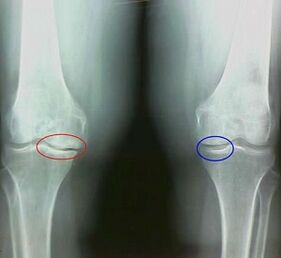

For example, what is the difference between arthritis and arthrosis of the knee joint?With arthritis, the synovial shell of articular tissues occurs.This causes an increase in temperature in the joint.

The joint swells, a persistent pain syndrome develops, intensifying during movement.With arthrosis, the pain occurs only after physical activity, you can hear a characteristic crunch or clicks in the joint, gradually the joint is deformed and loses mobility.